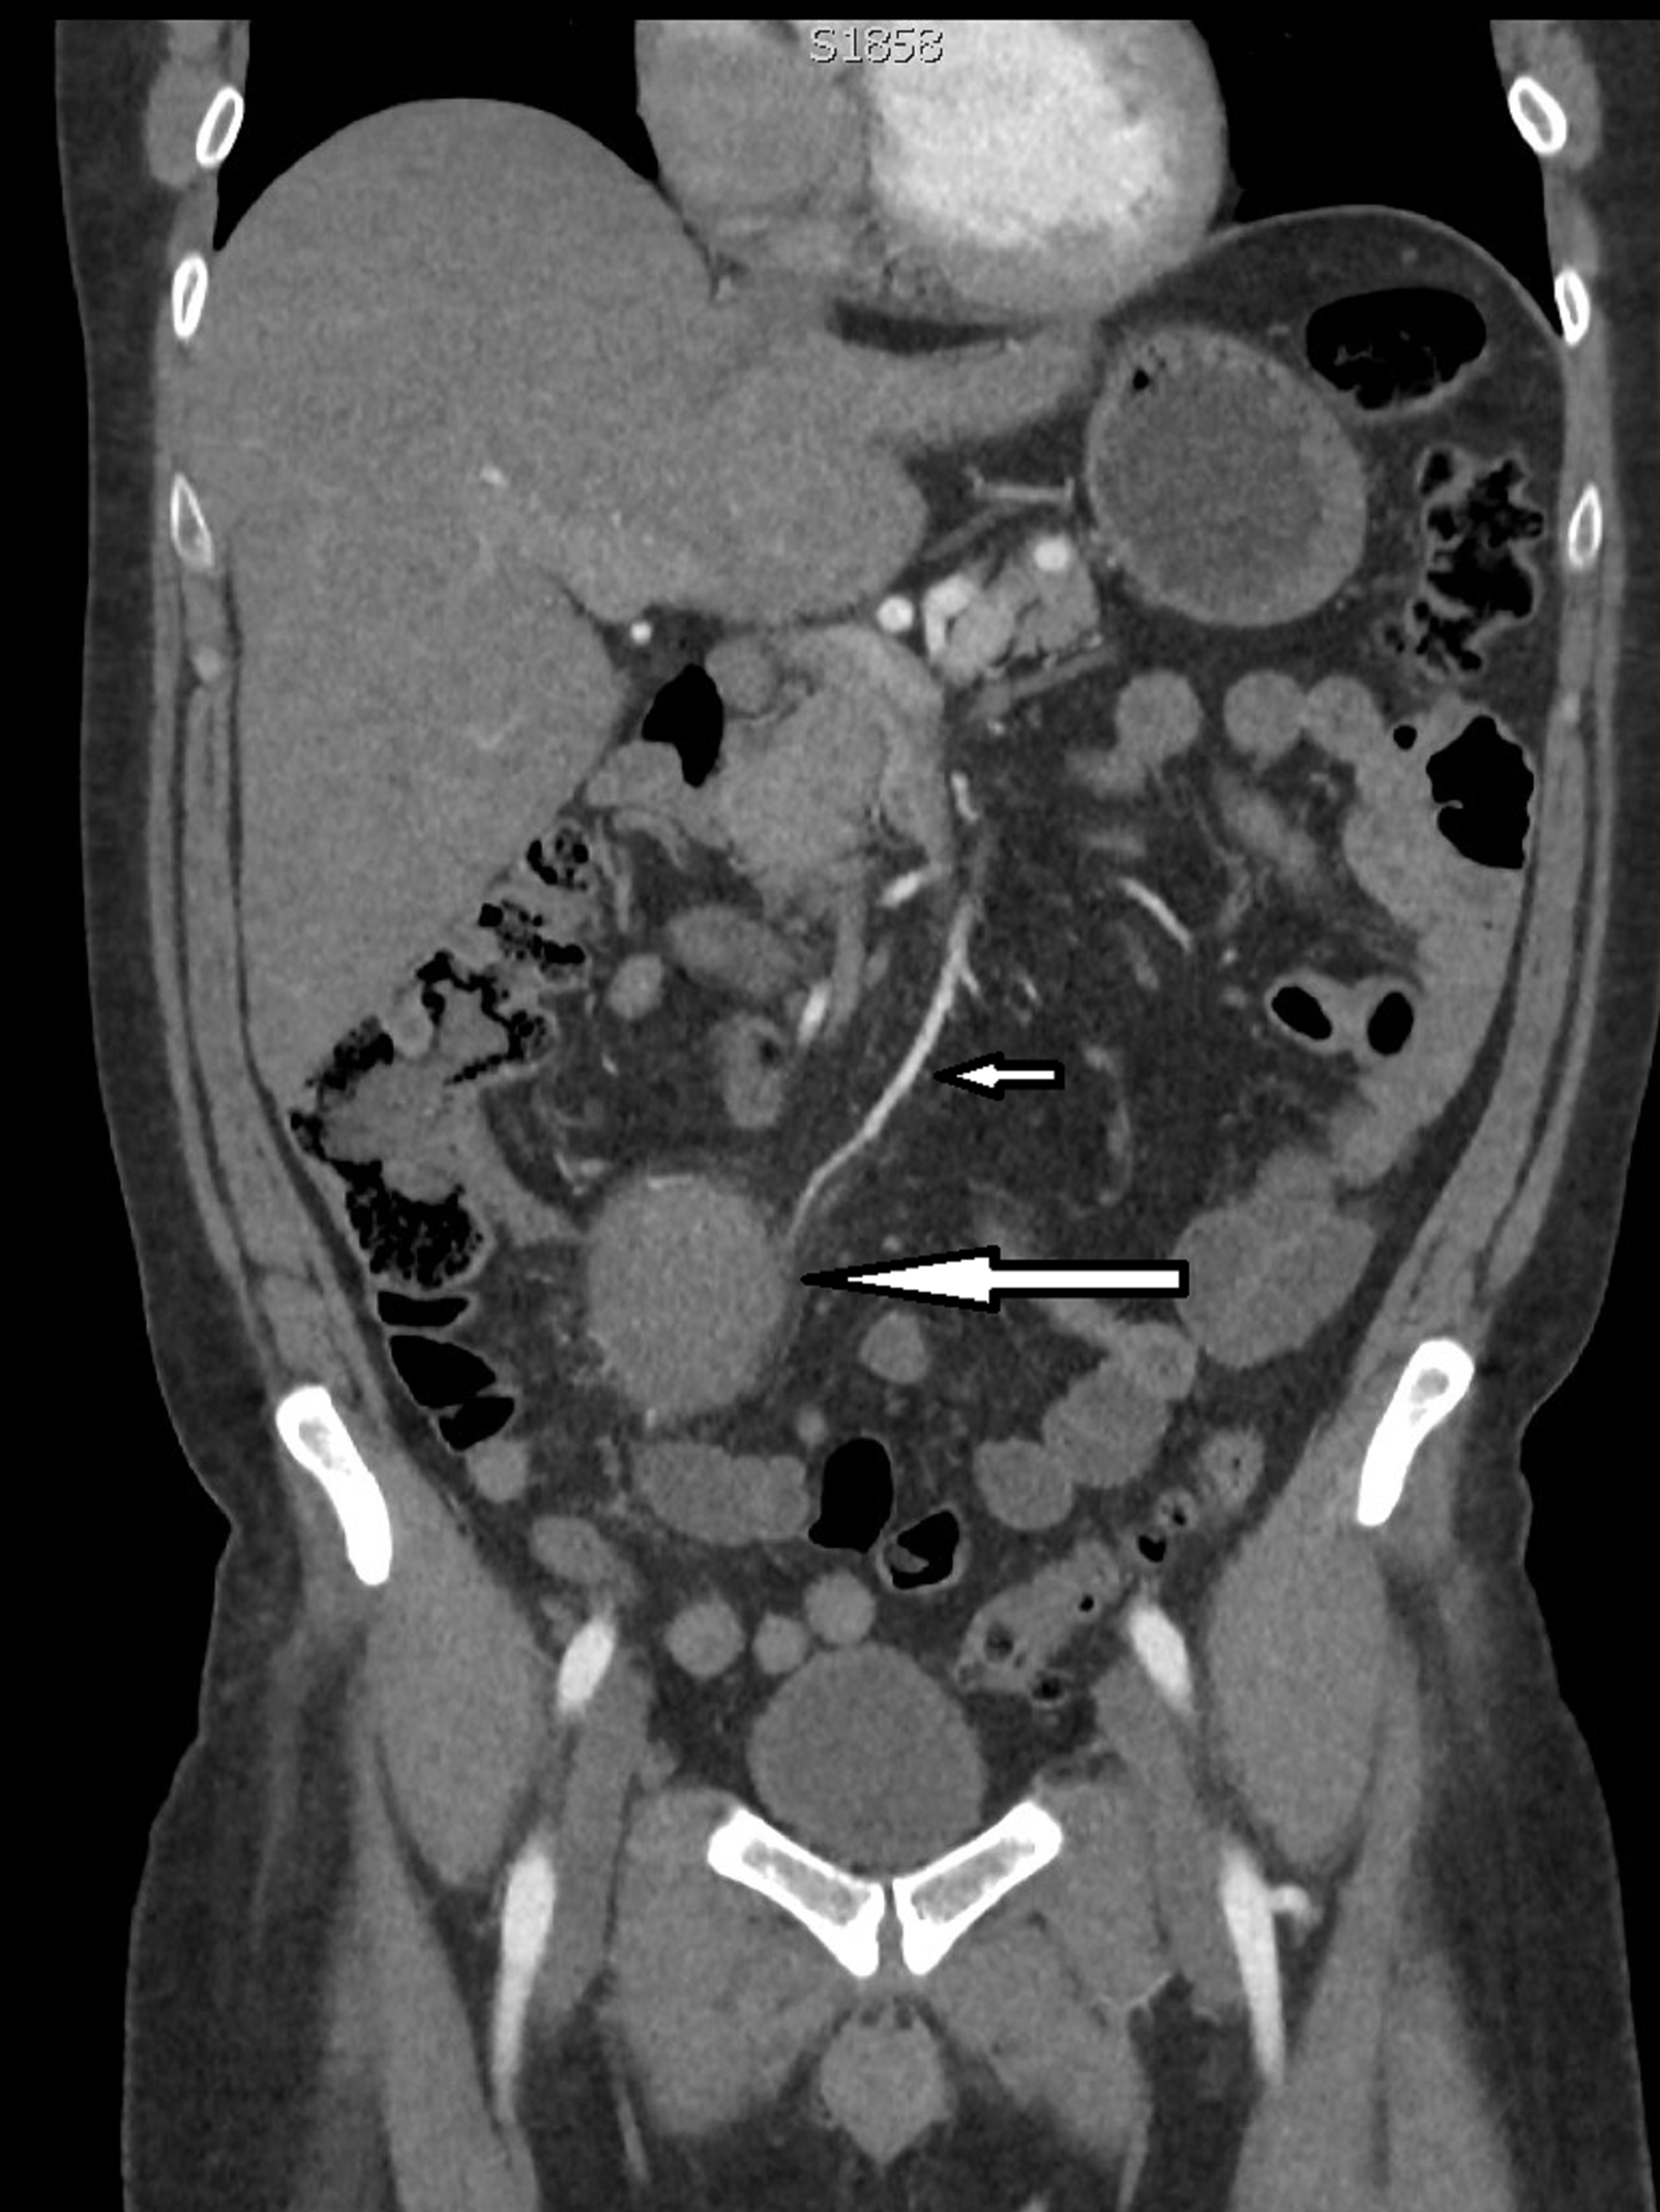

Superior Mesenteric Artery Syndrome Nhs. The syndrome may be precipitated by sudden weight loss secondary to other pathologies such as. Often acute occlusion of the SMA restricts blood flow to the midgut resulting in intestinal ischaemia. Superior Mesenteric Artery Syndrome Rani Sophia and Waseem Ahmad Bashir Yeovil Hospital NHS Foundation Trust Yeovil Somerset United Kingdom 1. Superior mesenteric artery syndrome SMAS Wilkie syndrome or cast syndrome is a rare condition that usually presents with symptoms of mid to upper gastrointestinal obstruction due to the compression of the duodenum between the abdominal aorta posteriorly and the superior mesenteric artery anteriorly.

Superior mesenteric artery syndrome SMAS is a digestive condition that occurs when the duodenum the first part of the small intestine is compressed between two arteries the aorta and the superior mesenteric artery.

A Systematic Review of Case Reports. Eating a liquid dietsoft foodchew things several yes lat on left side after food and during pain backup in fetal position during pain and rest. Rare syndrome characterized by symptoms resulting from vascular compressionobstruction of third part of duodenum in angle between aorta and superior mesenteric artery 1 clinical symptoms include nausea vomiting and post-prandial epigastric abdominal pain with or without associated weight loss and anorexia 1. Superior mesenteric artery syndrome SMAS Wilkie syndrome or cast syndrome is a rare condition that usually presents with symptoms of mid to upper gastrointestinal obstruction due to the compression of the duodenum between the abdominal aorta posteriorly and the superior mesenteric artery anteriorly. There are a number of cause of superior mesenteric artery occlusion including thrombosis embolism abdominal aortic aneurysm and aortic dissection. 1 Symptoms vary based on severity but can be severely debilitating.

Superior mesenteric artery syndrome is a rare digestive system disorder. Superior mesenteric artery syndrome is a gastro-vascular disorder in which the third and final portion of the duodenum is compressed between the abdominal aorta and the overlying superior mesenteric artery. It crosses over the first part of the small intestine called the duodenum. New Reply Follow New Topic. This rare potentially life-threatening syndrome is typically caused by an angle of 625 between the AA and the SMA in comparison to the normal range of 3856 due to.